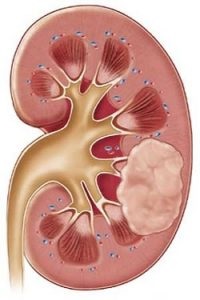

Există o patologie numită adenom de rinichi. Aceasta este o tumora benigna, care se află în stadii incipiente de dezvoltare nu are loc, și într-o stare de neglijare poate fi renăscut în oncologie.

Rinichi adenom - o tumoare benigna, aceasta se dezvoltă lent, consistența gros, cu limite clare. Educația este dimensiunea de doi milimetri la treizeci de milimetri.

În cazul în care patologia depășesc aceste limite, atunci putem vorbi despre maligna a tumorii. În plus, nu este întotdeauna posibil să se facă distincția de educație oncologie maligne, folosind un studiu diferențial.

Imediat ce adenomul de rinichi este crescută, ea începe să se comprime vasele de sange, perturbarea circulației și terminatiile nervoase, crescând astfel durerea. În plus, această patologie este ușor de palpat.

Datorită faptului că o tumoare mică, și o creștere lentă, aceasta nu poate fi detectat în stadii incipiente de dezvoltare. În această etapă, ea poate fi diagnosticată întâmplător în timpul unei inspecții de rutină prin ultrasunete.